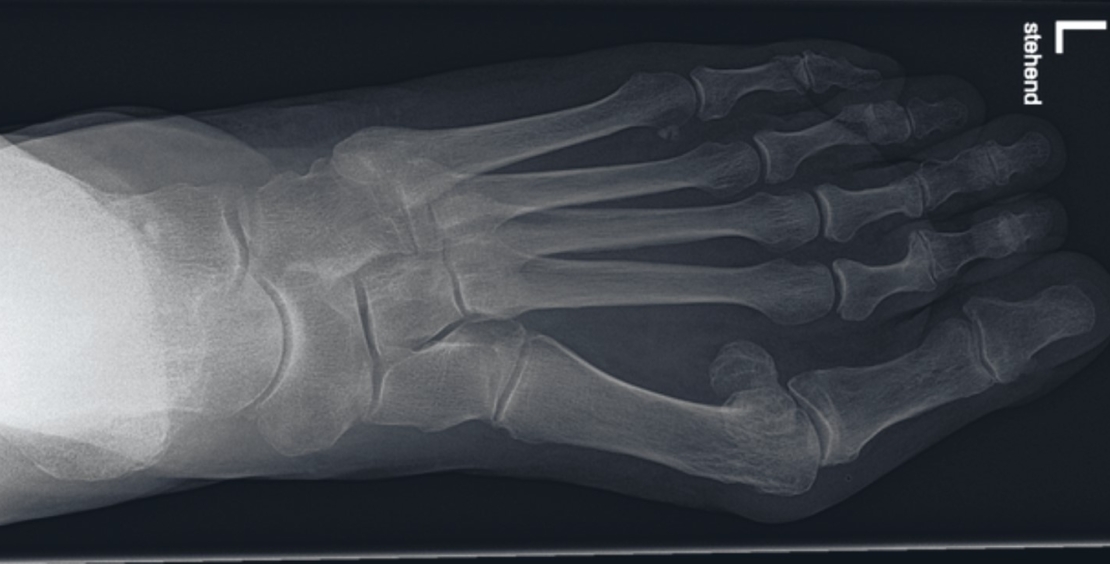

Ein konventionelles, im Stehen durchgeführtes, Röntgenbild der Füsse in drei Ebenen (dorso-plantar, lateral und schräg) kann anatomische Ursachen der Metatarsalgie erfassen. Dieses wird auf eine Hallux-valgus-Fehlstellung/ Arthrose im MTP-I-Gelenk, eine Überlänge vom 2. Strahl bzw. kurzes Metatarsale I, Stressfrakturen, Arthrose oder Nekrosen sowie (Sub-)Luxationen der Metatarsophalangealgelenke beurteilt.